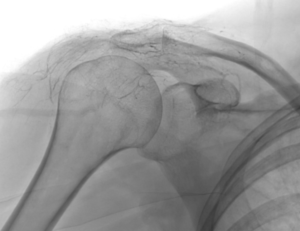

Artériographie épaule Lipiojoint

Grâce à l'imagerie de précision (angiographie), le radiologue interventionnel identifie ces vaisseaux « anormaux » et les occlut sélectivement. En bloquant leur flux sanguin, on réduit l'apport en oxygène et nutriments à la zone enflammée, favorisant une résolution rapide des symptômes.

2. Guidage par imagerie : Le cathéter est avancé jusqu'à l'artère sous-clavière sous contrôle radioscopique en temps réel.

4. Vérification : Angiographie de contrôle pour confirmer le succès.